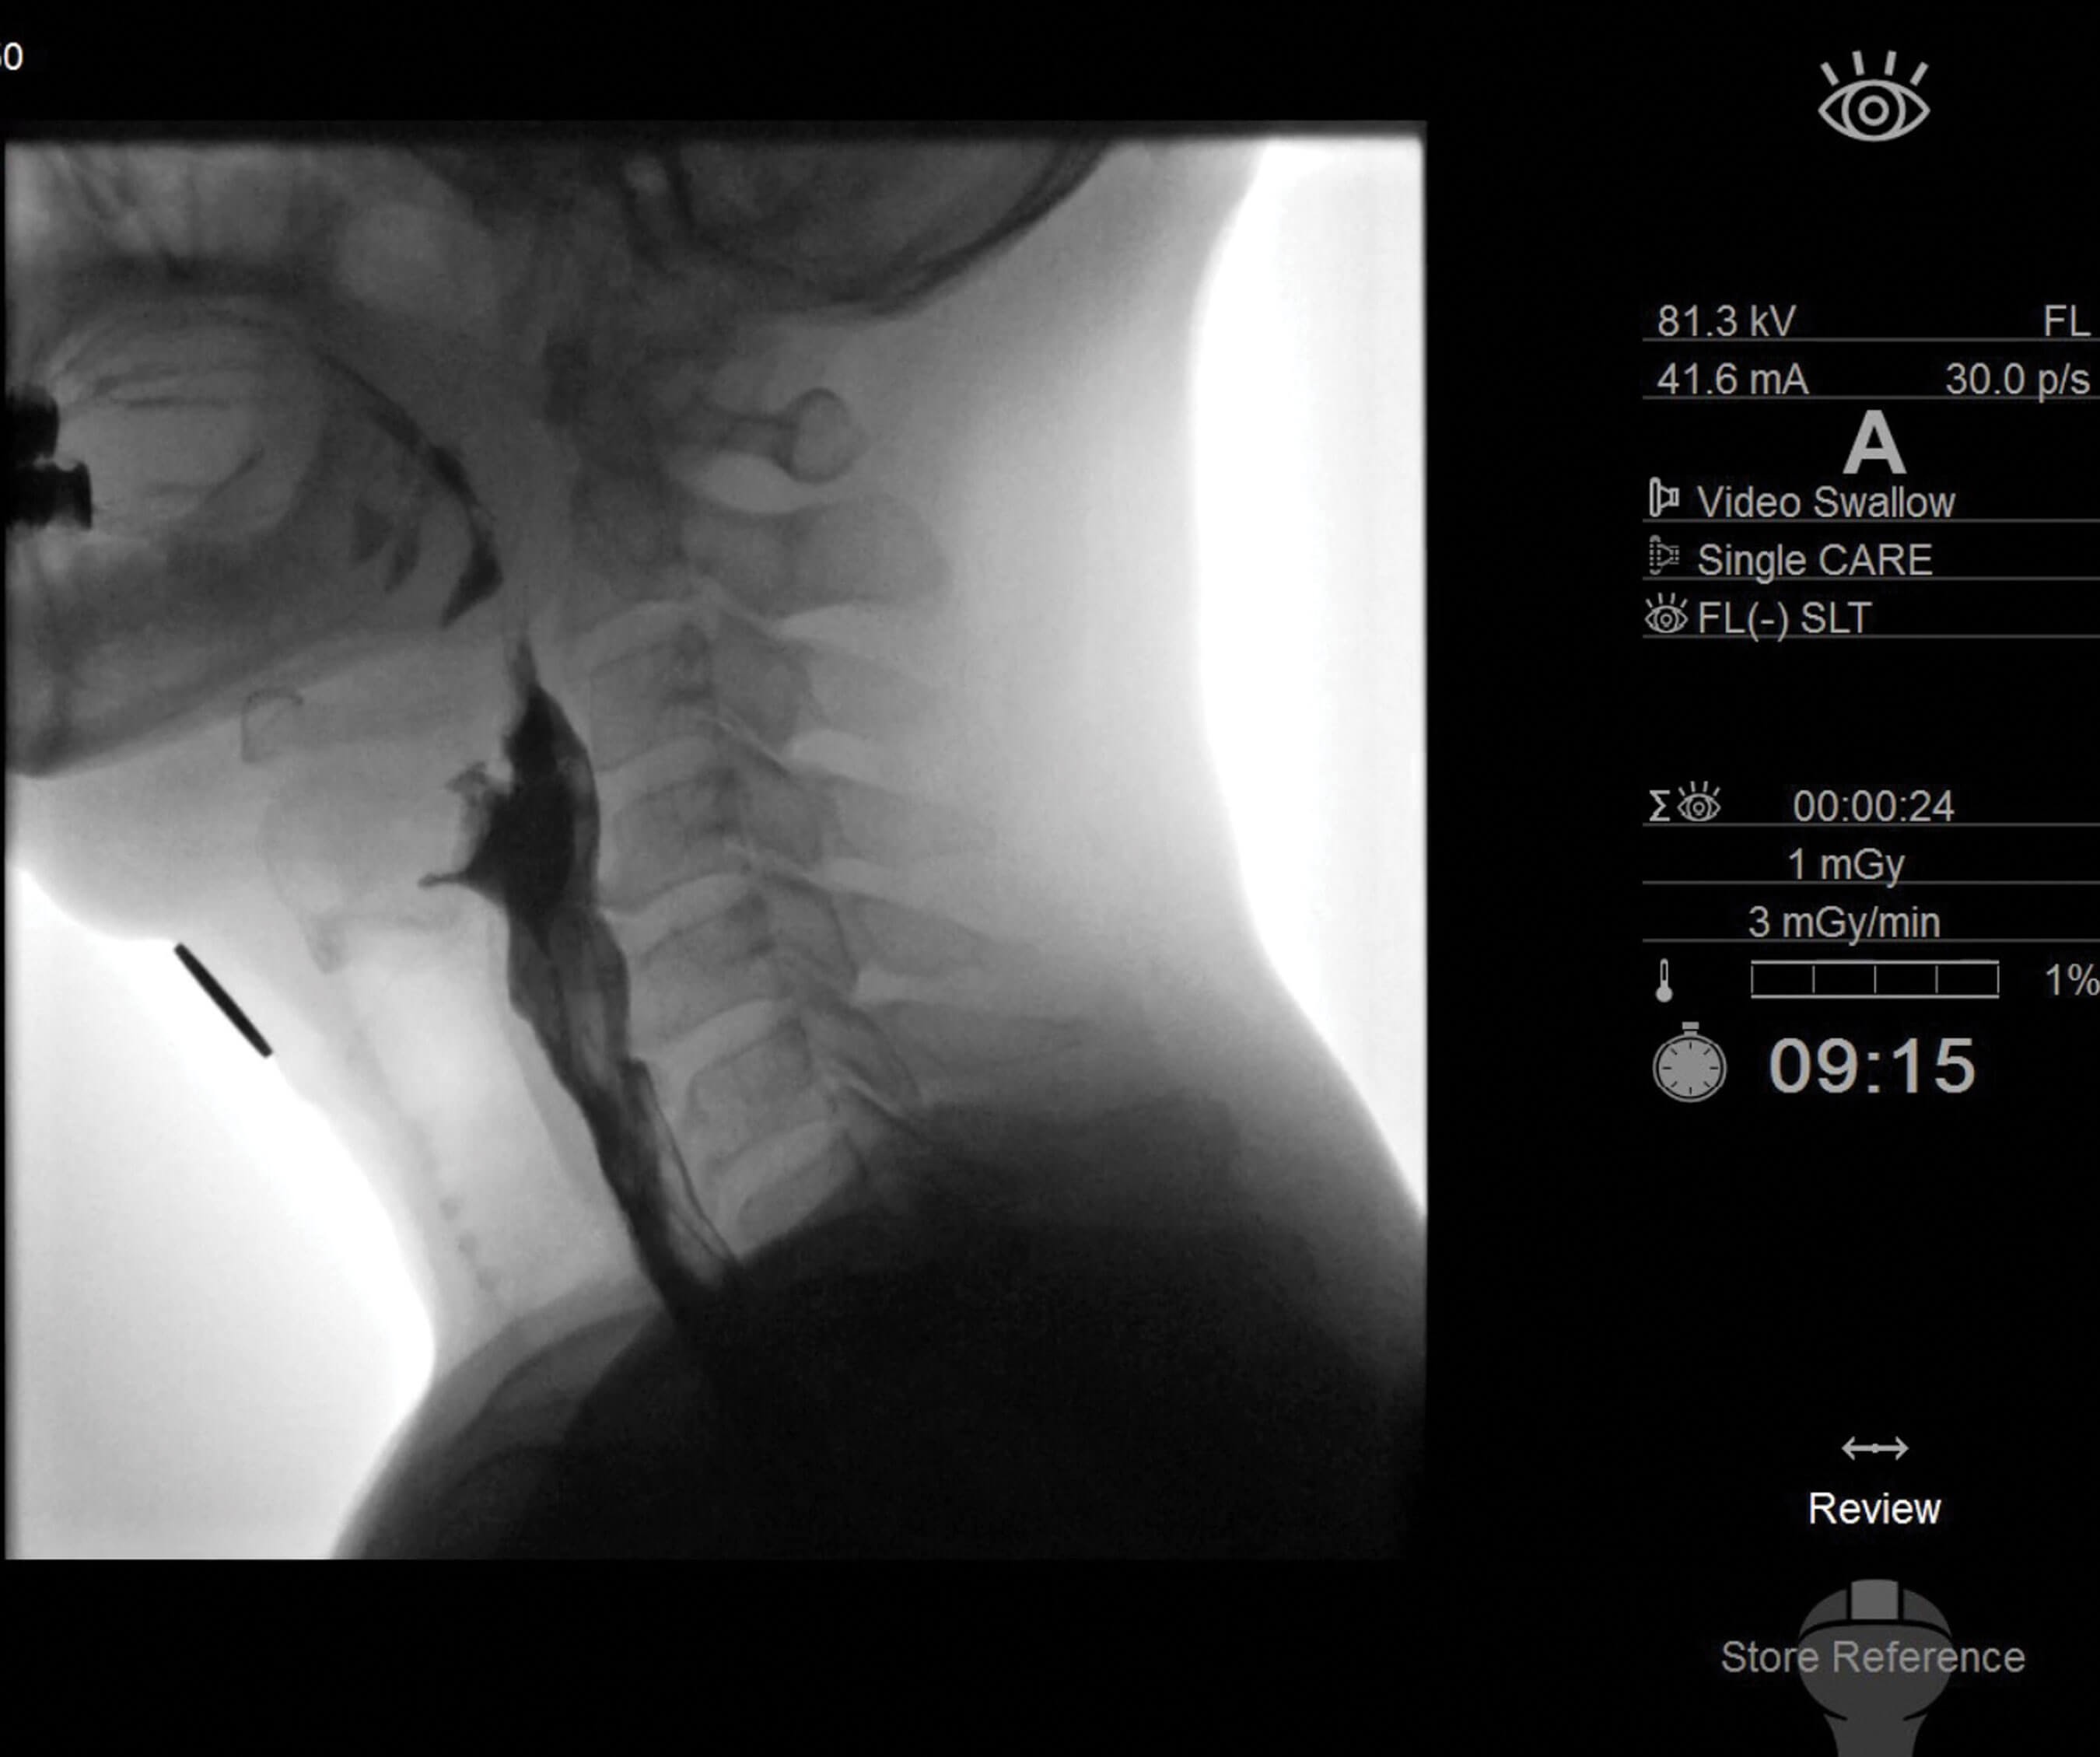

Taking life by the throat

Patients suffering with problems with their voice, airway and/or swallowing can find their symptoms immensely distressing, and their care places a huge burden on healthcare systems. We hear from a world-leading laryngologist on current and future directions. Field of interest...